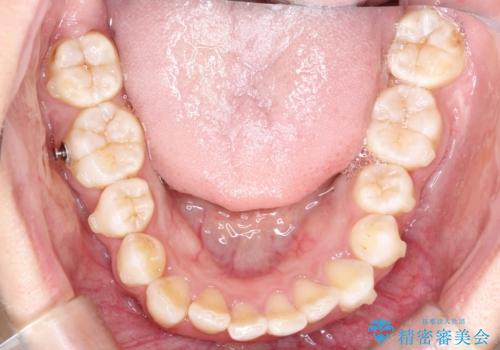

重度のガタガタのインビザラインによる非抜歯矯正

- 全体的なガタガタを気にされて来院されました。

抜歯矯正も考えられる状態でしたが、ご本人的になるべく歯を抜かない矯正を希望されました。

奥歯を後方に移動させるのと、歯と歯の間にわずかに隙間を作ることでスペースを確保して、抜歯をせず歯を並べる計画としました。

ガタガタの度合いが大きかったので少し時間がかかりましたが、非常に協力的な患者様でしたので、抜歯をせず計画通りに治療を終えることができました。